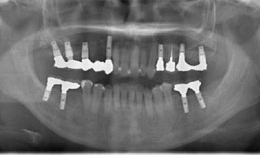

上顎

保存困難な歯を抜歯後、サイナスリフトを行いインプラントを7本埋め込んで、セラミックスクラウンを被せた

下顎

インプラントを4本埋め込んで、セラミックスクラウンを被せた

インプラント フィクスチャー11本 285,000円×11=3,135,000円(税抜)

上部構造

(ハイブリッドクラウン)11本

135,000×11=1,485,000円(税抜)

サイナスリフト 200,000円(税抜)